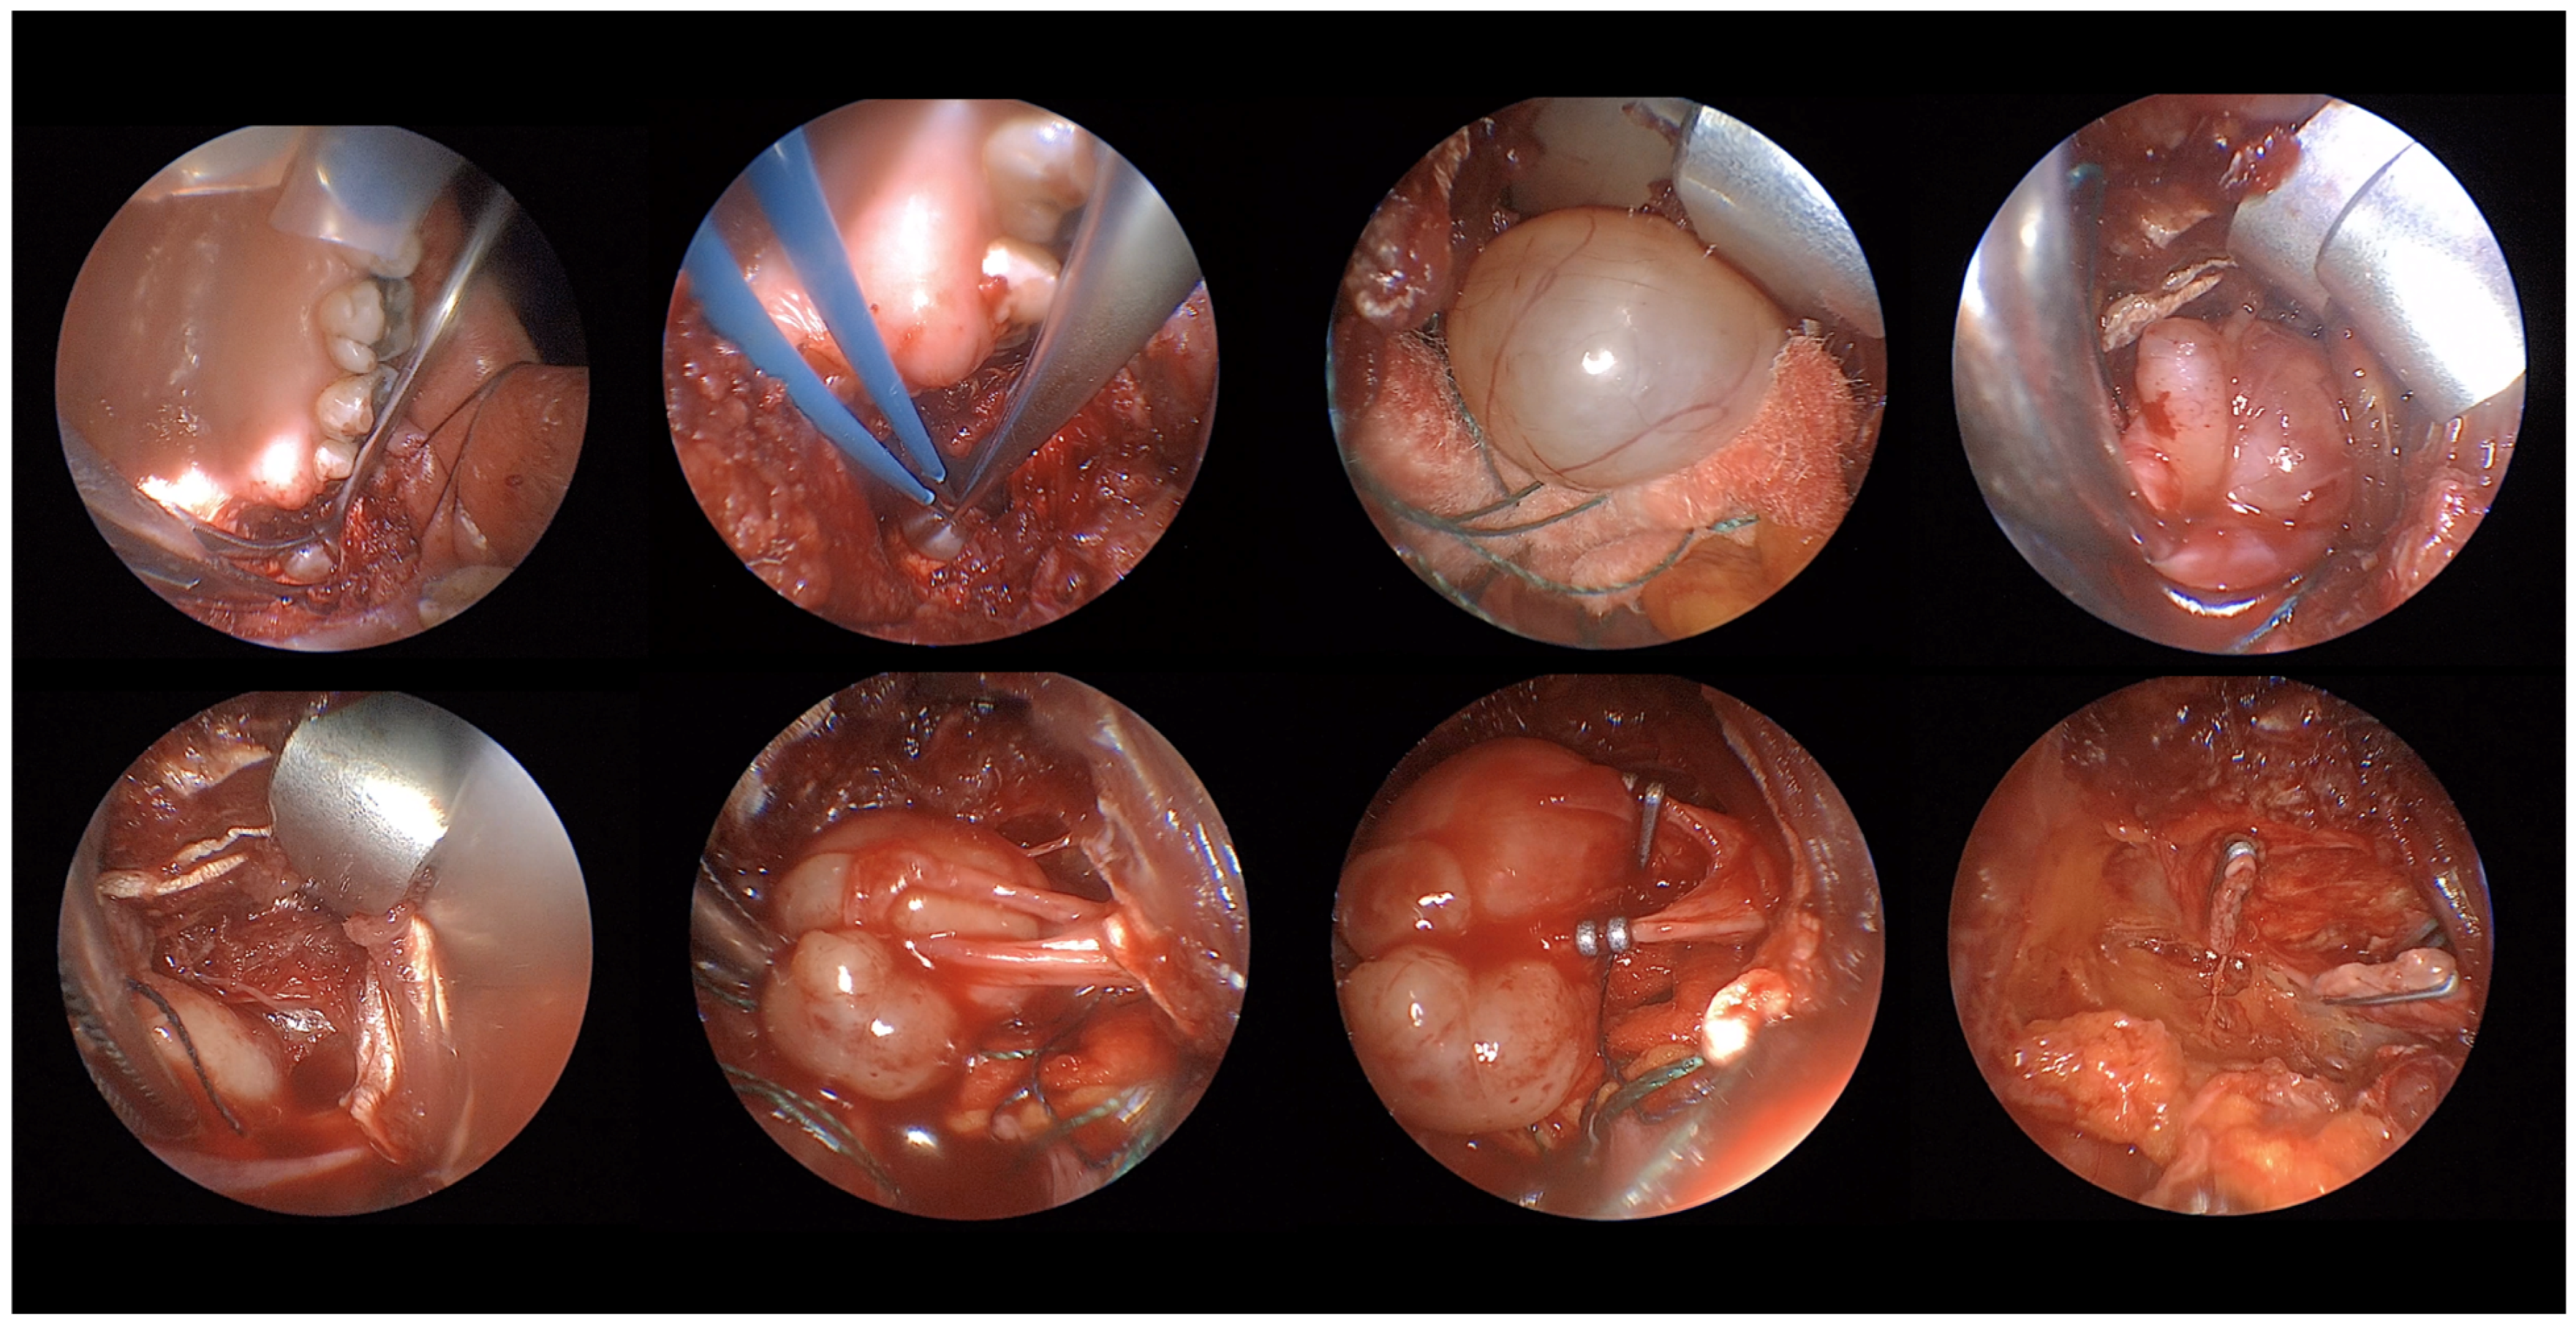

Overall, based on what we observed in this case series, EATA presents several advantages. Firstly, it is an excellent view of the operatory area and allows for clear identification of the mass and surrounding structures, easy identification of the vessels and their clamping, excellent control of the bleeding, and easy evaluation of the result post-mass removal (Figure 7). What emerges from this case series is that lesions amenable to a transoral corridor, potentially with endoscopic assistance, include encapsulated tumors of the true PPS that present with oropharyngeal bulging, anteromedial medialization of parapharyngeal fat, and posterior displacement of major vessels (primarily pleomorphic adenomas); encapsulated benign tumors of the carotid PPS that present with oropharyngeal bulging but exhibit an atypical vascular displacement pattern (i.e., posterior displacement of major vessels, despite being carotid space lesions), a class primarily comprising schwannomas; encapsulated tumors of the masticator space, even if they do not present with intraoral bulging; and encapsulated lesions protruding into the rhino-oropharyngeal lumen where major vessel displacement is not a concern. Magnetic Resonance Imaging (MRI) with a contrast agent plays a crucial role in the differential diagnosis of these spaces and in defining the characteristics of the lesions in question, in addition to its ability to exclude vascular lesions by highlighting flow voids.

Figure 7. The figure shows all the advantages of using an endoscope for transoral approach. From up-left to down-right the endoscope allows to identify the mass, to immediately cauterize small vessels to maintain clean the area, the full visualization of finding and its capsule and its posterior relationship. Moreover, the clear visualization of the vascular structures of the tumor allows an easy clamping with consequent excellent bleeding control at the end of the surgery.